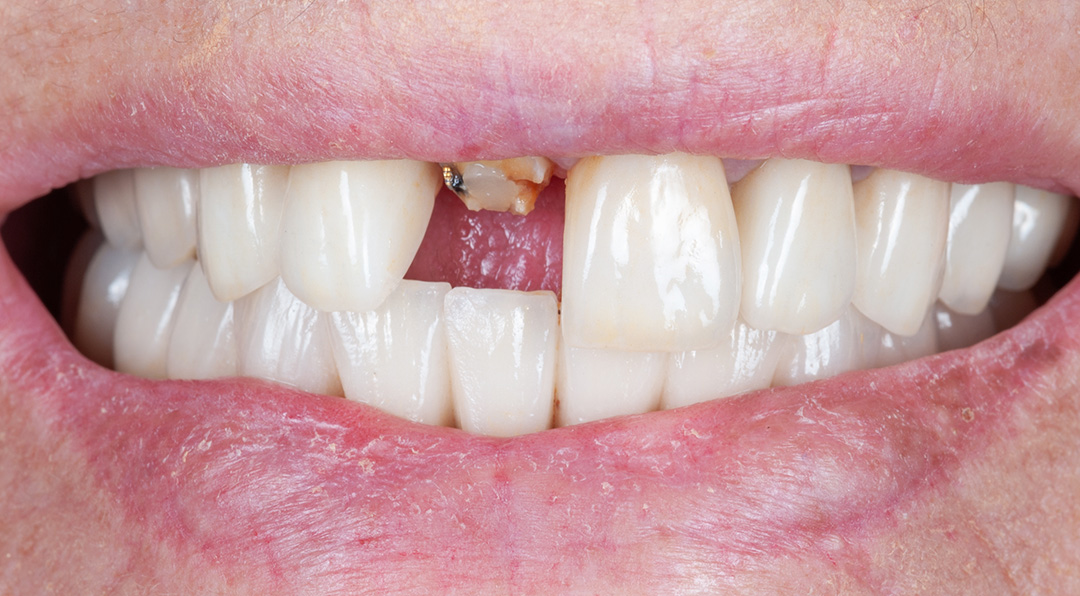

A 67-year-old female patient presented with a broken central incisor. The tooth in question had been restored with a crown several years ago, but this had since detached. The patient did not report being in pain, though she was concerned about the appearance of her smile. Her initial assessment revealed no relevant medical history and she was a non-smoker.

Surgery and initial outcomes

The remaining root was carefully and atraumatically extracted using a Benex® pull-out device. The surgical guide was fitted in the mouth and a CONELOG PROGRESSIVE-LINE implant with conical connection was immediately placed, torqued to above 50 Ncm for high primary stability. The space between the implant and the facial cortical bone plate was filled with MinerOss XP biomaterial and a connective tissue graft was tunnelled around the neck of the implant. This was harvested from the tuberosity, de-epithelialised, and added around the neck of the implant. The objective of this procedure was to ensure long-term papilla stability and prevent both the future collapse of the soft tissue and opening of the embrasures. This is paramount when restoring a gap in the anterior zone.